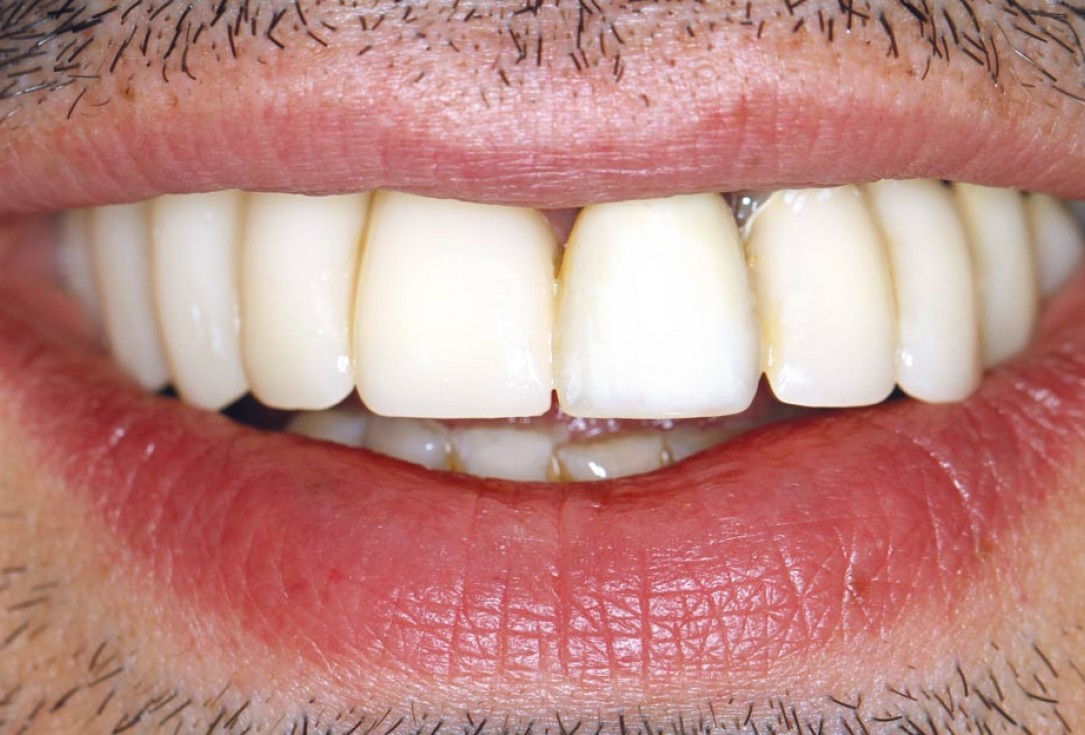

Initial situation - endodontically failing tooth 22, very thin biotype, high lip line and esthetic expectations